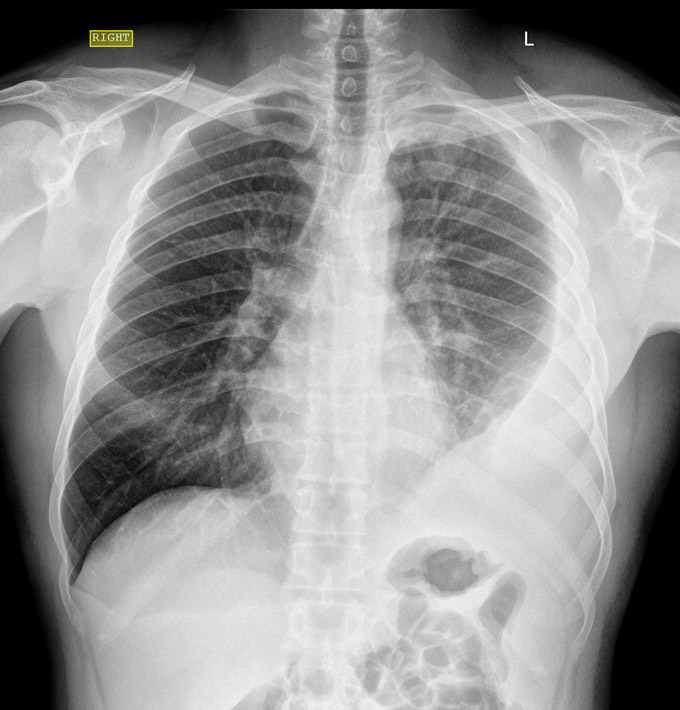

Para quem está em busca de informações sobre doenças pulmonares, derrame pleural é um tópico que merece atenção.

A doença se caracteriza pela presença de água na pleura, uma membrana transparente e bem fina, formada por duas camadas, e que reveste o interior da parede torácica e os pulmões.

O acúmulo de líquido ocorre no espaço entre a pleura visceral e a pleura parietal, e pode causar uma série de complicações.

É importante que esta condição não seja confundida com o que chamamos de "água no pulmão”, já que, neste caso, o acúmulo de líquido acontece dentro do pulmão propriamente, e não entre as pleuras.